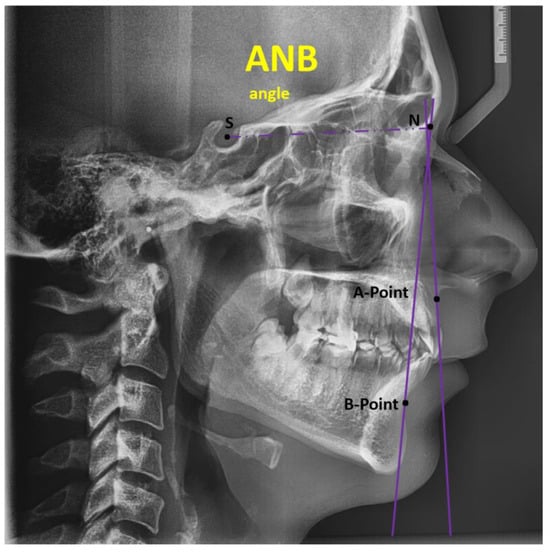

| ANB (degrees) | 4.53 (2.65, 7.00) |